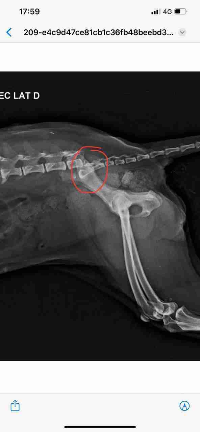

Me chamo Júlio. No dia 28/02/24 minha cadela Princesa caiu de uma altura de mais ou menos 5 metros e fraturou a coluna, na imagem do Raio-X é nítido que quebrou. Fizemos consultas e exames, porém não temos condições de desembolsar o valor de 4mil reais, fora o valor dos medicamentos e internação.

Ela tem 12 anos de idade e faz 13 anos em Maio, a raça é Poodle. Ela caiu de costas e quebrou a coluna, seu movimento do rabo e das patas traseiras se perderam. Tentei arrecadar o valor para antes da cirurgia, mas não consegui, mas ainda preciso pagar o resto, que ficou em 3200 reais, dividi em 5 vezes apenas, e a conta total junto com a internação deu R$ 5,075.